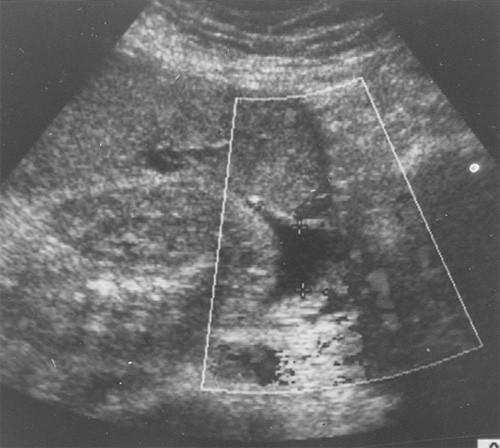

Learn the essential sonographic techniques for assessing oligohydramnios and its clinical implications. This course covers causes such as intrauterine growth restriction, fetal anomalies, and preterm rupture of membranes. Understand the role of ultrasound in diagnosis, management, and prenatal care to optimize fetal outcomes.

Learn the various sonographic definitions of oligohydramnios.